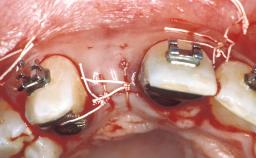

Replacement of an Upper Right Central Incisor with a Regular Neck Implant, Restored with an All-Ceramic Crown, Transocclusally Screw-Retained

This 37-year-old female patient, a non-smoker, complained about discomfort and gingival problems at tooth 11. She was in good general health, and her medical history was without significant findings. The clinical inspection of the oral cavity revealed a fistula originating at tooth 11. Radiological examination of the crowned tooth 11 re- vealed a root-canal filling, status after apicoectomy, and a large periapical bone defect, as well as secondary caries. The adjacent teeth, 21 and 12,were periodontally healthy. They had interdental composite fillings that the patient wanted replaced. The bone crest levels of teeth 12 and 21 well maintained, providing potential soft-tissue support.